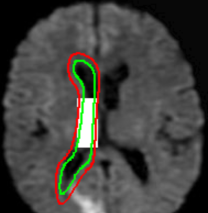

Refer to captionRefer to caption(a)(b)Refer to captionRefer to caption(c)(d)Refer to captionRefer to caption𝑎𝑏Refer to captionRefer to caption𝑐𝑑\begin{array}[]{cc}\includegraphics[width=112.0187pt,height=114.33119pt]{Ultra_init-1.pdf}&\includegraphics[width=112.0187pt,height=114.33119pt]{Ultra_Res-1.pdf}\\ (a)&(b)\\ \includegraphics[width=112.0187pt]{Ultra_init-2.pdf}&\includegraphics[width=112.0187pt]{Ultra_Res-2.pdf}\\ (c)&(d)\end{array}

Figure 13: Segmentation of endocardium in B-mode ultrasound images. (a) and (c) show the initializations provided, (b) and (d) show the converged contours. Image source: (a) was taken from [38] and (c) was taken from [39] .

In Figure 13, we show the results for segmentation of endocardium in B-mode ultrasound images, an imaging modality where shape prior information is popularly[40, 41] used to counter the problem of broken/diffuse boundaries between the region of interest and its background. In Figure 14, we show an example where the template based formulation is able to overcome partial loss of signal due to occlusion and still segment the object reliably. We observe that, by incorporating prior knowledge of the shape, we can segment images with partial loss of structure and broken boundaries.